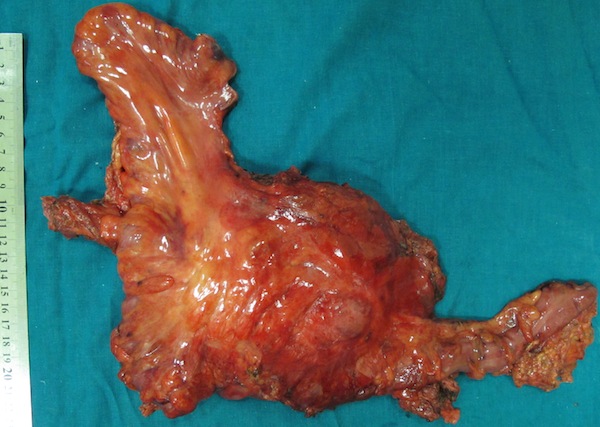

06.06.2013г. – операция: комбинированное удаление рецидива опухоли лоханки левой почки с краевой резекцией левой общей подвздошной вены, резекция стенки мочевого пузыря, резекция ободочной кишки, формирование трансверзоректоанастомоза: Под сочетанной (см. протокол анестезии), в положении на спине, после обработки операционного поля, произведена верхненижнесрединная лапаротомия длиной 30 см по старому послеоперационному рубцу. При ревизии брюшной полости отмечается образование в ложе удаленной левой почки, плотной консистенции, не смещаемое, с вростанием в брыжейку нисходящего отдела ободочной кишки, интимно прилежащее к поджелудочной железе, брюшному отделу аорты, подвздошным сосудам слева, вростающее в левую поясничную мышцу. Выполнена резекция ободочной кишки (30 см) с помощью прямого степлера, сформирован анастомоз по типу конец в конец с помощью циркулярного сшивающего степлера. С техническими сложностями опухоль отделена тупым и острым путем от поясничной мышцы, подвздошных сосудов. С техническими сложностями выполнена мобилизация общей подвздошной вены с краевой резекцией, одномоментной кровопотерей до 1 литра. Выполнена резекция стенки мочевого пузыря с устьем левого мочеточника. Мочевой пузырь ушит двурядным швом. Опухоль, культя левого мочеточника, резецированная стенка мочевого пузыря, резецированная ободочная кишка, лимфатические узлы удалены ad block. Контроль гемостаза, целостности окружающих органов, инородных тел в ране. Послеоперационная рана послойно ушита с выведением ПХВ дренажей из ложа удаленной опухоли через контраппертуру, в малый таз через параректальную область слева. Послойный шов раны, асептическая повязка. Общая кровопотеря 3500 мл.

Гистологическое исследование 12114-78 от 17.06.2013г. (ad block: удаленная опухоль, культя левого мочеточника, резецированная стенка мочевого пузыря, резецированная ободочная кишка, лимфатические узлы): инвазивный умеренно дифференцированный уротелиальный рак высокой степени злокачественности (G2 с участками G3). Рецидив в зоне выполненной нефрэктомии в 2008 г. по поводу рака лоханки левой почки (по клиническим данным). опухоль представлена кистовидным образованием размерами до 16х8х8 см, с собственной толстой фиброзной капсулой толщиной до 3-4 см, в проствете кистовидного образования – множественные обильные очаги разрастания опухолевой ткани. Глубина инвазии опухоли – до 21/2-2/3 толщины ее собственной капсулы, за ее пределы опухоль не проростает. Снаружи кистовидное образование окружено жировой клетчаткой, к нему тесно прилежит удаленный фрагмент толстой кишки. толстая кишка, включая ее края резекции – без признаков опухолевого роста. Культя мочеточника – без признаков опухолевого роста, со склеротическими изменениями. Выявлено 15 прилежащих лимфатических узлов – без признаков опухолевого роста, с реактивным синусовым гистиоцитозом. Гистологическое исследование 12099-113 от 17.06.2013г. (клетчатка из области общих подвздошных сосудов слева): фрагменты жировой клетчатки с лимфатическими узлами (выявлено 12 лимфатических узлов) – без признаков опухолевого роста, с реактивным синусовым гистиоцитозом и с очаговой реактивной фолликулярной гиперплазией).